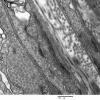

PERIPHERAL NEUROPATHY

1 NORMAL NERVE ANATOMY

4 Normal Electron Microscopy